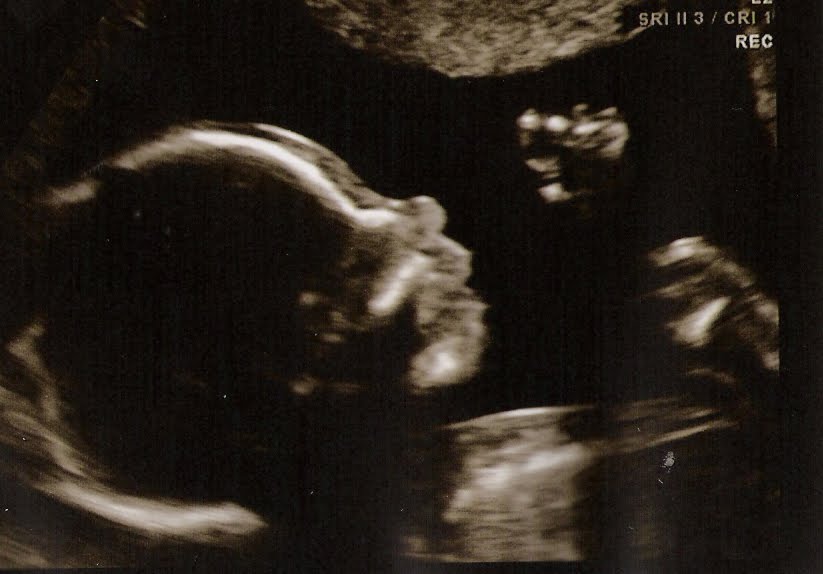

Words do not express how we felt as we watched our baby on the screen at our ultrasound today. Our baby girl is perfect and healthy and beautiful. She weighs 15 oz now and was “talking” to us by opening and closing her mouth for most of the ultrasound. We can’t wait to welcome Haley Lynn into our family in September.

We got some great video but the files are too big to convert so I can’t upload them. We also saw some 3-D images, which was unexpected.